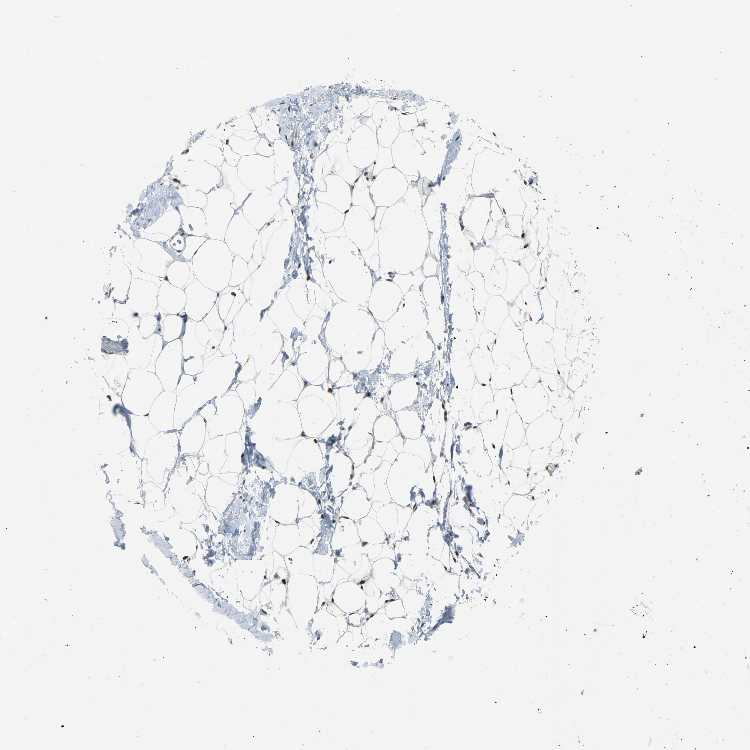

BREAST - Antibody stainingi

Antibody staining in the annotated cell types in the current human tissue is reported as not detected, low, medium, or high, based on conventional immunohistochemistry profiling in selected tissues. This score is based on the combination of the staining intensity and fraction of stained cells.

Each image is clickable and will lead to virtual microscopy that enables deeper exploration of all samples and also displays staining intensity scores, fraction scores and subcellular localization as well as patient and tissue information for each sample.

Antibody CAB004282

Adipocytes Low

Glandular cells Not detected

Myoepithelial cells Not detected